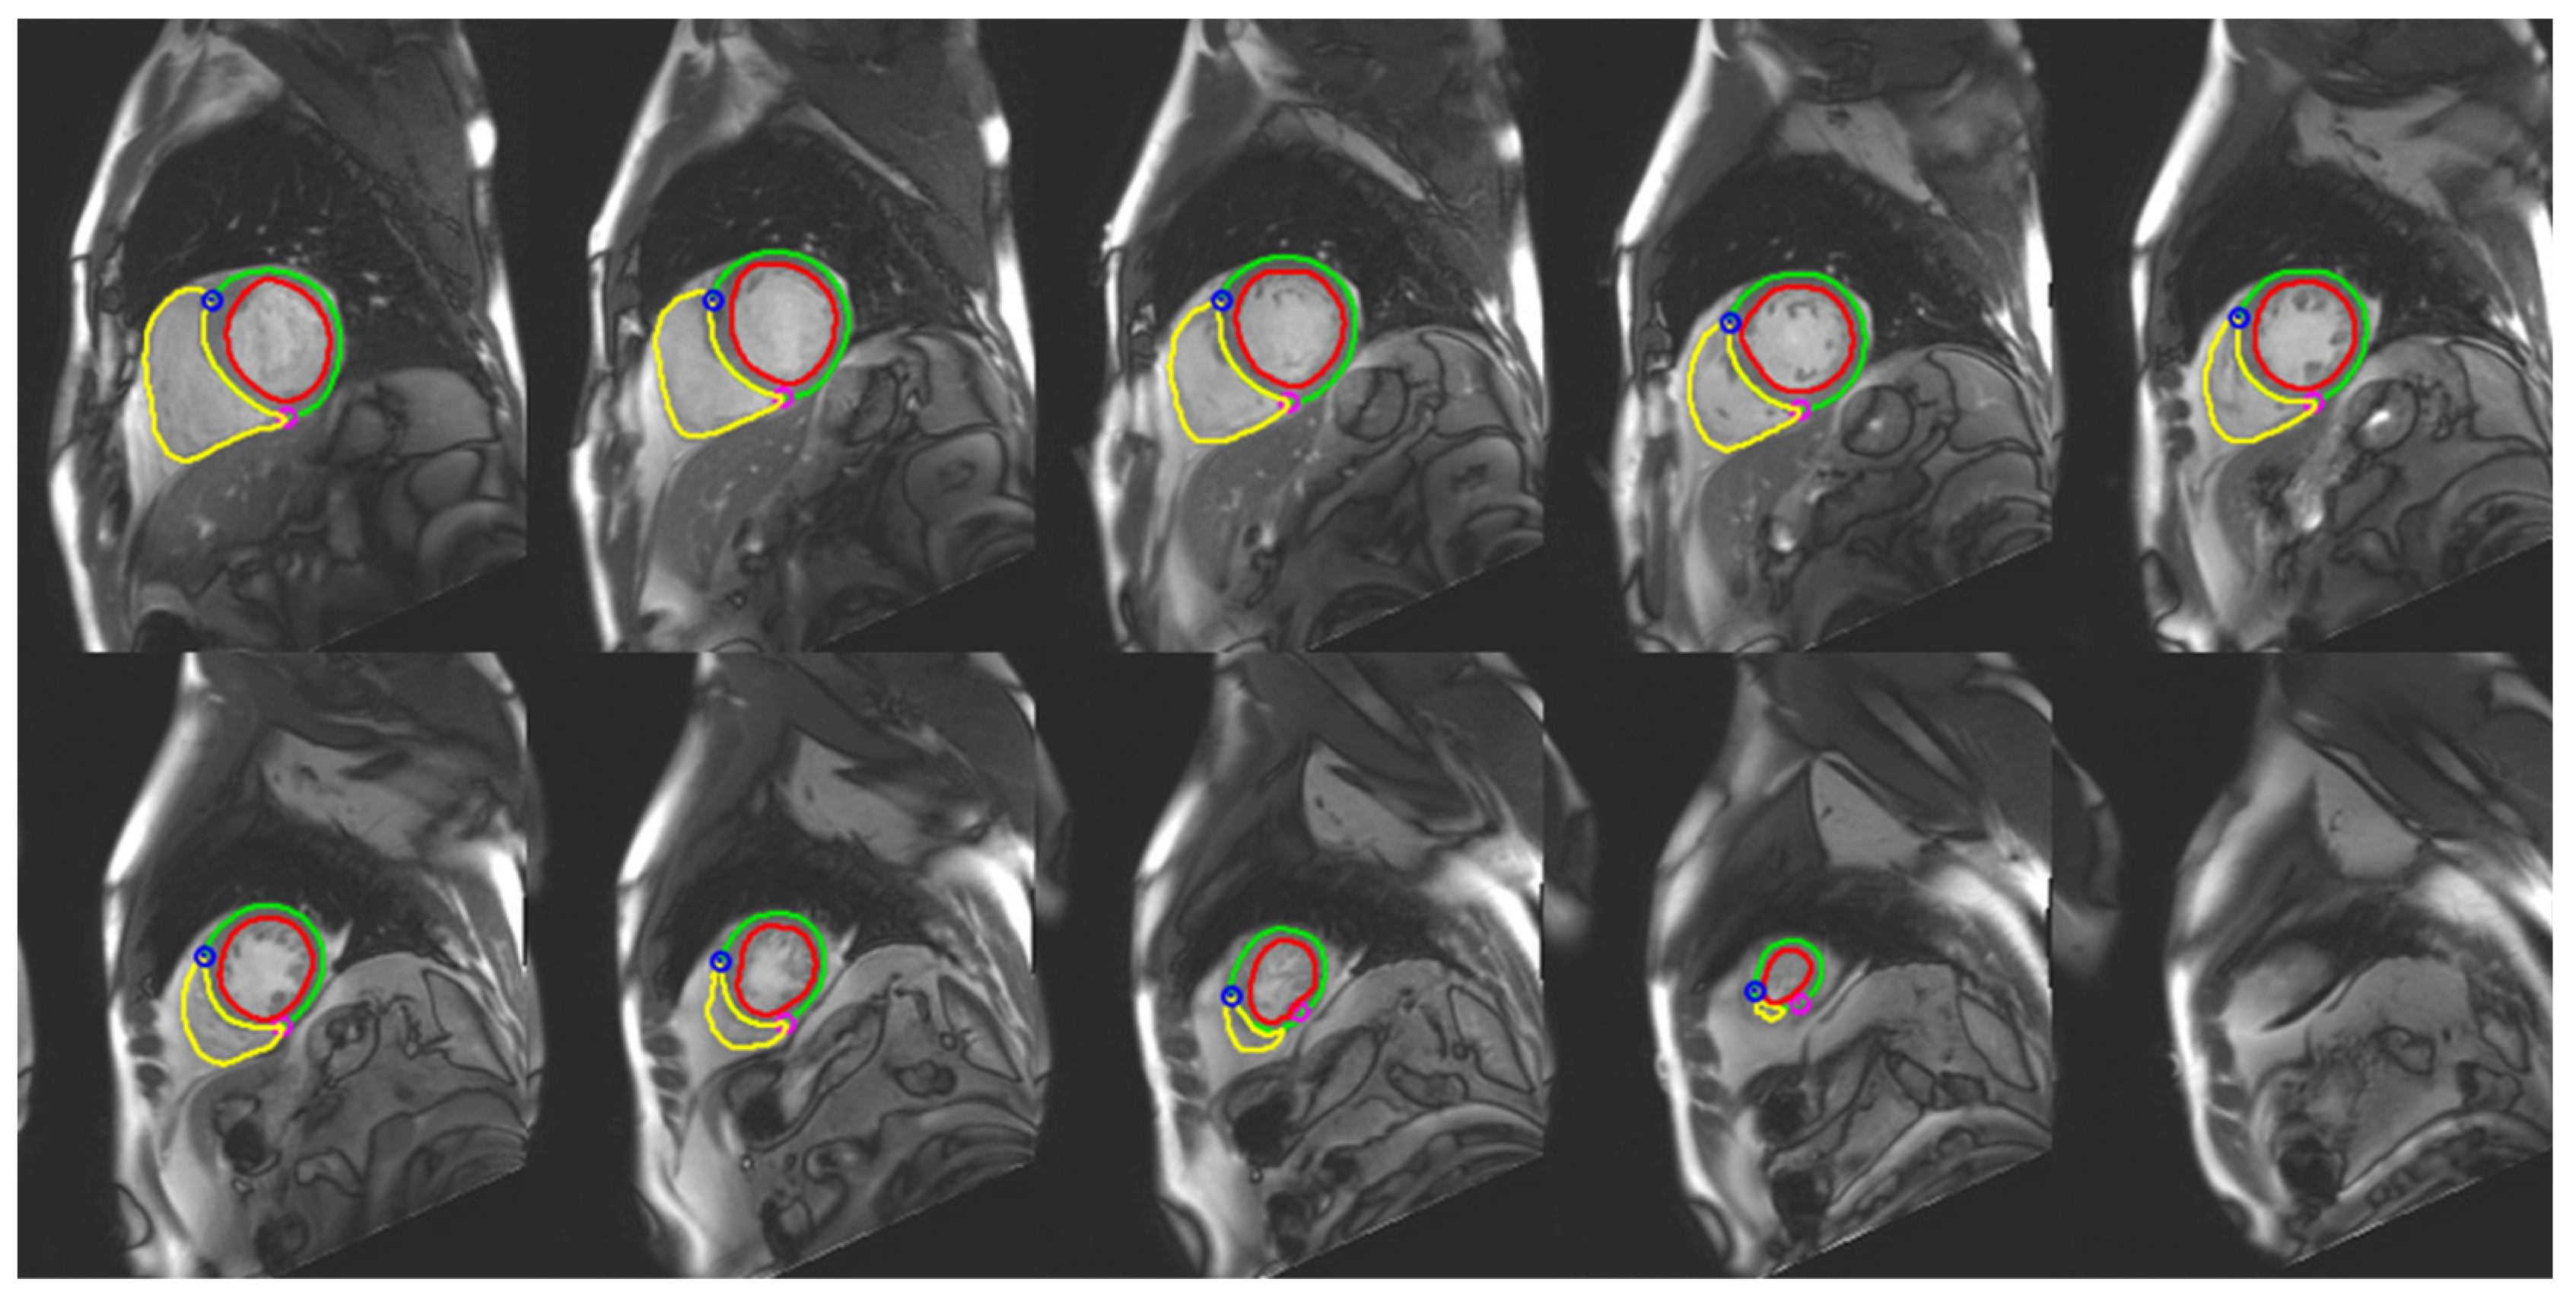

Different AI models have been developed to automate the segmentation process, making it easier, faster, and more accurate (Figure 2).

Figure 2.

AI-based segmentation of right and left ventricles in end diastolic phase in a 55-year-old patient.

During the 20th International Conference on Medical Image Computing and Computer Assisted Intervention (MICCAI), the “Automatic Cardiac Diagnosis Challenge” (ACDC) was performed to establish the best AI model for automatic cardiac segmentation. Bernard et al. tested multiple DL algorithms for the segmentation and classification task [58]. They demonstrated a 0.97 correlation score for the best algorithm, which proved to work very well for LV segmentation, but it was suboptimal for right ventricle and myocardial evaluation.